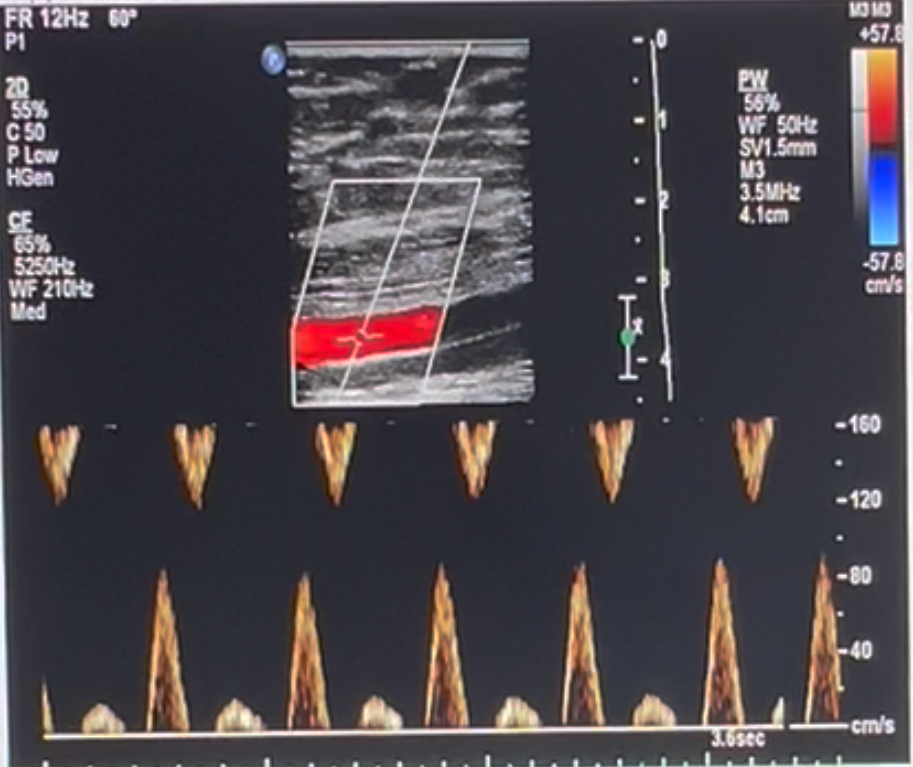

Which of the following machine settings will improve the attached image?

a. activate electronic focusing

b. activate electronic steering

c. decrease sample volume size

d. decrease color persistence

activate electronic steering